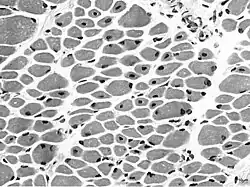

Muscle biopsy from the quadriceps taken at 3 months of age from a girl with X-linked centronuclear ("myotubular") myopathy due to a mutation in the myotubularin (MTM1) gene and extremely skewed X-inactivation (H&E stain, transverse section). Note marked variability in fibre size, moderate increase in connective tissue and numerous central nuclei.

Centronuclear myopathy manifests on muscle biopsy as centrally located nuclei encircled by a perinuclear halo filled with aggregates of glycogen and mitochondria but without myofilaments.[10] All muscles, including extra-ocular muscles, have the distinctive central nucleus,[11] which can affect up to 90% of the fibers.[12]